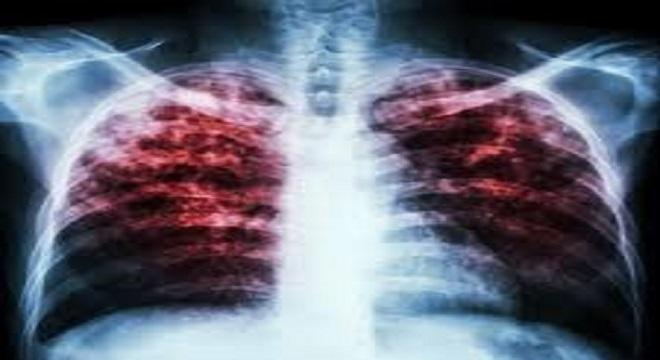

La tuberculosis

Esta enfermedad bacteriana se asocia con pobres condiciones sanitarias, hacinamiento y carencias en los servicios de salud. La vacunación de los niños con la vacuna BCG, ofrece una adecuada protección contra este patógeno.